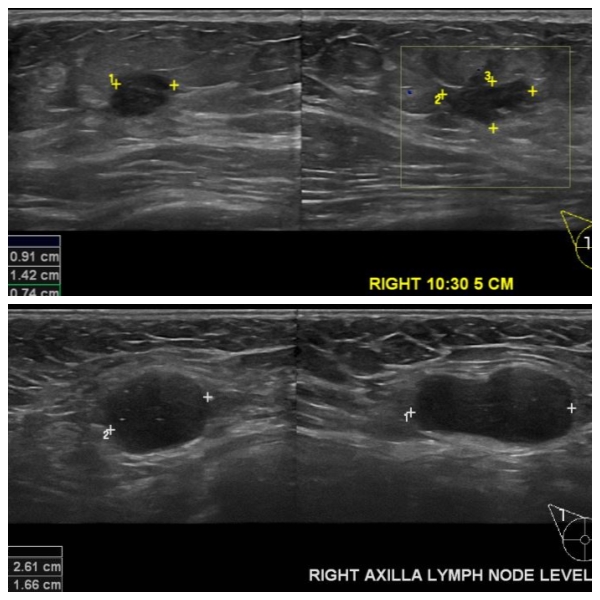

상기 환자 우측 유방 통증과 겨드랑이 멍우리로 내원하신 50대 여성 분으로  우측

10시 30분 방향 5cm 떨어진 거리의 혹 조직검사 시행하여 우측 침윤성 유관암 진단 되었으며 , 우측 겨드랑이 림프절비대 세침검사 시행하여 전이암으로 진단 되었습니다.